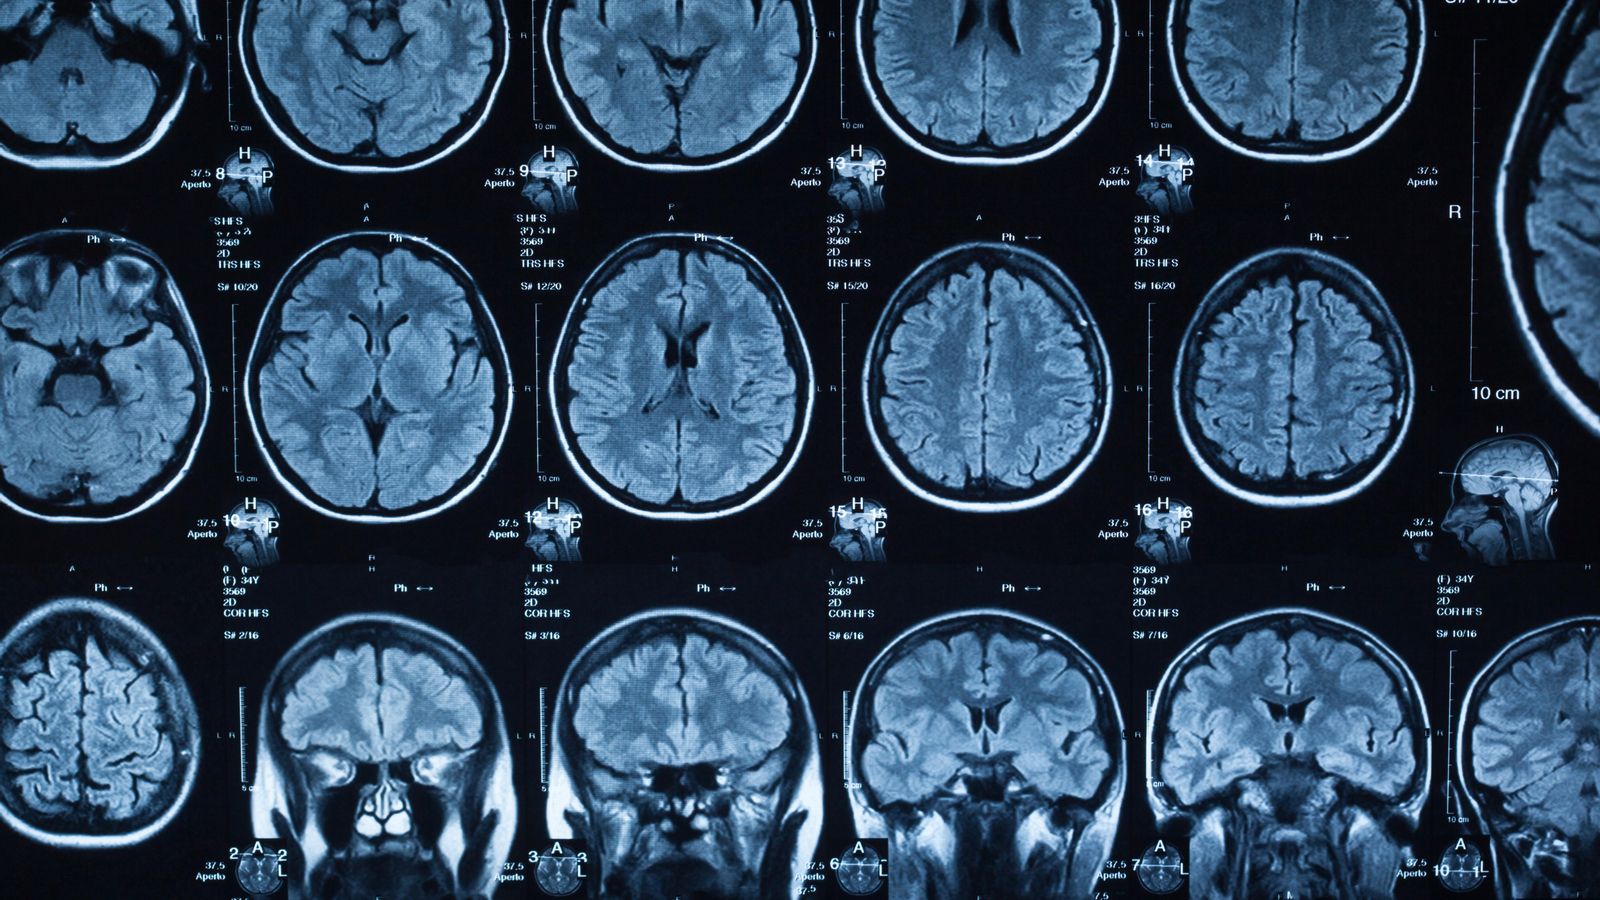

L'ictus pot produir-se per l'hemorràgia que genera el trencament d'un vas cerebral o per una disminució important del flux sanguini que rep el cervell. Aquest últim és l'isquèmic, el més freqüent, que representa el 85% del total.

El medicament, desenvolupat per la farmacèutica AptaTargets, té una funció neuroprotectora en bloquejar la resposta inflamatòria que el cos produeix després d'un ictus.

A més, la dosi alta d'ApTOLL va aconseguir reduir el volum final de l'infart i va millorar les puntuacions al cap de 72 hores en funció de l'escala NIHSS, que serveix per a quantificar el dèficit neurològic després d'un accident vascular cerebral agut.